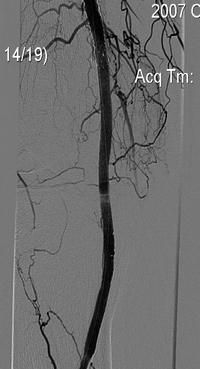

Произведена реканализация правой подколенной артерии и правого ТПС внутри ранее имплантированных стентов гидрофильным проводником, затем ЧБА с использованием баллона Opta Pro 4 x 40 mm с повторным стентированием стентами Smart и постдилатацией Opta Pro 6 x 60mm.